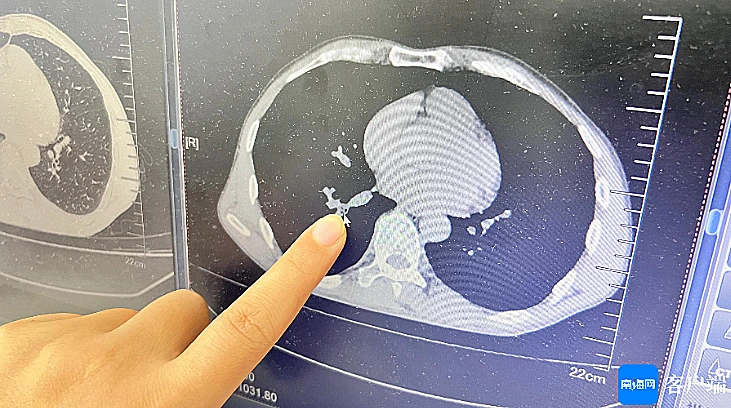

החרק התגלה בסופו של דבר בריאה הימנית של המטופל. הרופאים ביצעו ברונכוסקופיה טרום ניתוחית באמצעות צינור דק לבדיקת דרכי הנשימה.